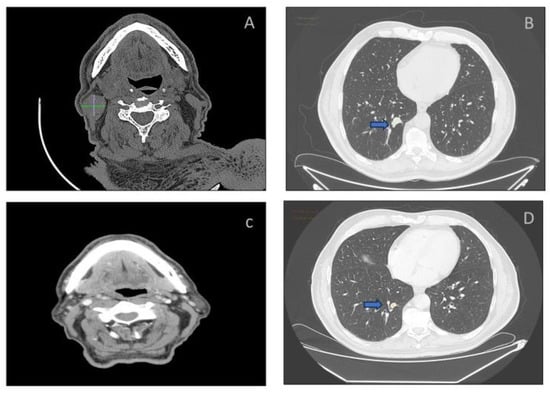

(A) Scattered groups of thyrocytes, with complex architectural and cytological atypia, including papillary-shaped group and atypical “histiocytoid” cells (inset) (Papanicolaou staining, ×20 magnification). (B) Representative amplification curves by real-time polymerase chain reaction (PCR) for DNA samples from wild-type BRAF (red curve) and BRAF V600E single-nucleotide mutation specimens (purple curve). Compared to wild-type BRAF, the BRAF V600E mutation sample required a greater number of amplification cycles (x axis) to reach a maximal signal intensity. The second case concerned a 67-year-old man who came to our institution for a routine check-up following a total thyroidectomy for a radioiodine refractory high-grade differentiated papillary thyroid carcinoma (HGDTC). The CT scan showed a neck mass and a lung metastasis (Figure 5A,B). A FNA was performed on the neck mass, confirming the recurrence of the HGDTC. RT-PCR analysis performed on the FNA detected a BRAF p.V600E; thus, the patient was deemed eligible for combination therapy with BRAF and MEK inhibitors [14]. The follow-up CT scan after the first three months of therapy revealed a complete regression of the neck lump and a volumetric reduction of the lung metastasis (Figure 5C,D).

Figure 5.

CT scans confirming the presence of a neck mass (A) and a metastatic nodule in the lung ((B), arrow). CT scans after three months of BRAF and MEK inhibitors treatment showing complete lump regression in the neck (C) and reduction of lung metastasis volume in the lung (D), arrow.